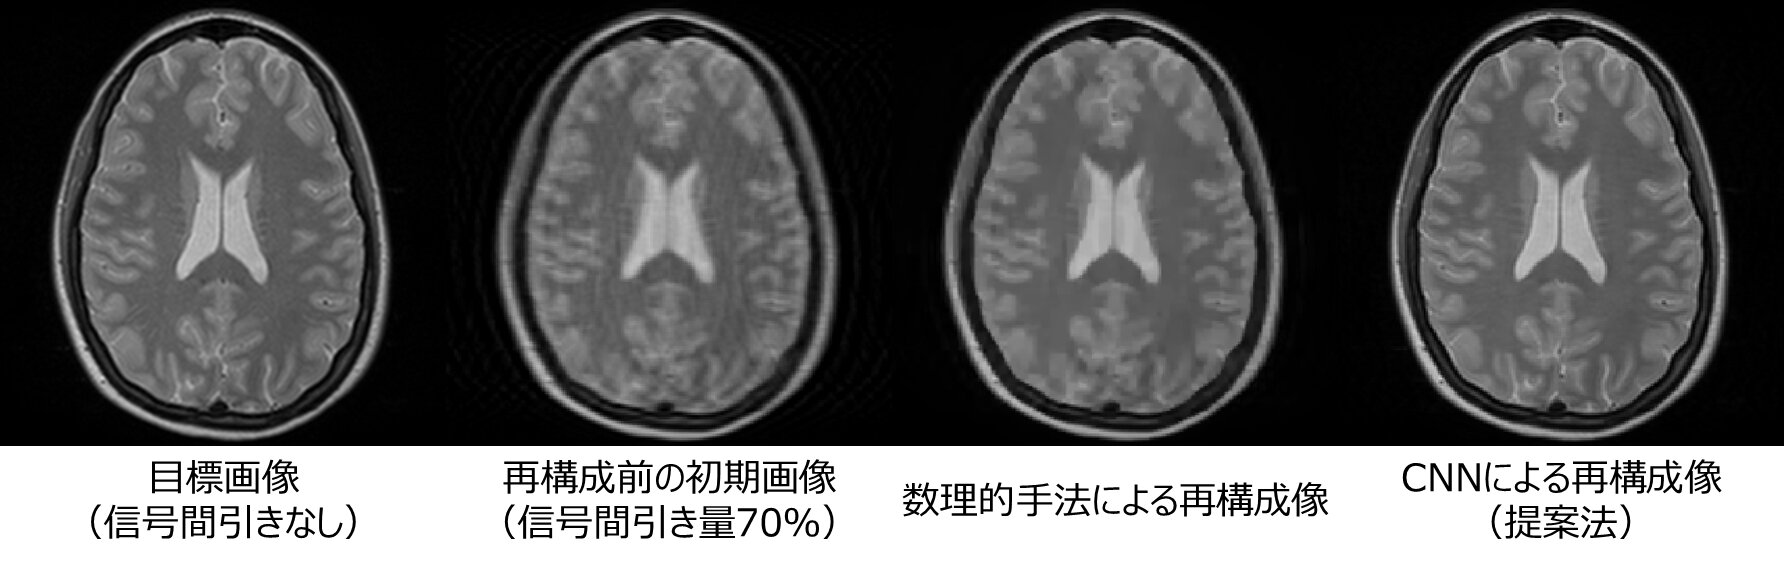

信号の間引きによって生じた乱れを抽出できるようにCNNに学習させ、再構成シミュレーションを行った。また、本手法との比較のために、従来手法である数理的な反復再構成法も併せて行った。シミュレーションの結果、本手法では信号間引きによって撮影を高速化した条件のもとで、画像1枚あたりの再構成時間を従来手法の十数秒から0.022秒に短縮できた。また、信号量を60~70%削減した場合に従来手法では構造的特徴の欠損、乱れ成分の残存や強い平滑化が見られたが、本手法では目標画像に近い高品質な画像が得られた(図2)。

【図2】